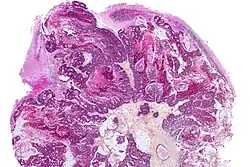

A brain metastasis is a cancer that has metastasized (spread) to the brain from another location in the body and is therefore considered a secondary brain tumor.[1][2] The metastasis typically shares a cancer cell type with the original site of the cancer.[3] Metastasis is the most common cause of brain cancer, as primary tumors that originate in the brain are less common.[4] The most common sites of primary cancer which metastasize to the brain are lung, breast, colon, kidney, and skin cancer. Brain metastases can occur months or even years after the original or primary cancer is treated. Brain metastases have a poor prognosis for cure, but modern treatments allow patients to live months and sometimes years after the diagnosis.[5]

Metastatic spread to the brain is usually hematogenous. Metastatic cells often lodge at the interface between gray mater and white mater as arteries narrow in caliber at this site. Spread to the meninges may result in leptomeningeal cancer.[11]